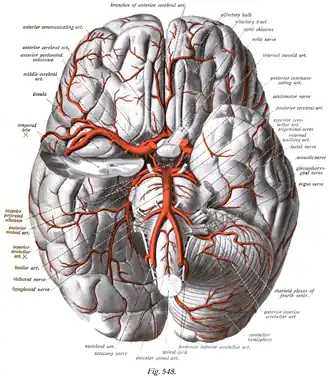

The leptomeningeal collateral circulation (also known as leptomeningeal anastomoses or pial collaterals) is a network of small blood vessels in the brain that connects branches of the middle, anterior and posterior cerebral arteries (MCA, ACA, and PCA),[1] with variation in its precise anatomy between individuals.[2] During a stroke, leptomeningeal collateral vessels allow limited blood flow when other, larger blood vessels provide inadequate blood supply to a part of the brain.[3]

Leptomeningeal collaterals lie within the leptomeninges, the two deep layers of the meninges called the pia mater and the arachnoid mater.[4] Their diameter has been measured at approximately 300 micrometers,[5] but there is variability between individuals in the size, quantity and location of these vessels, and between either hemisphere within the same subject.[6]

Inter-territorial end to end anastomoses exist between branches of the anterior cerebral artery and middle cerebral artery, the posterior cerebral artery and middle cerebral artery, the anterior cerebral artery and posterior cerebral artery, and the right and left anterior cerebral arteries.[7][8][9][10] Intra-territorial anastamoses connect adjacent arterial branches within the same arterial territory (between two branches of the same middle cerebral artery, for example).[5]

Inter-territorial leptomeningeal anastamoses between the posterior cerebral artery and anterior cerebral artery have been observed between the parieto-occipital branch of the posterior cerebral artery, and the precuneal branch or the posterior pericallosal branch of the anterior cerebral artery.[1]

Inter-territorial leptomeningeal anastamoses between the right and left anterior cerebral arteries have been observed between the right and left pericallosal arteries and the right and left callosal marginal arteries. Anastamoses have also been observed between precuneal branches originating from the middle portion of the pericallosal artery, or from the posterior portion of the callosal marginal branch of one side joining the opposite paracentral branch.[1]

Descriptions of leptomeningeal collateral vessels are found in Thomas Willis’ Cerebri Anatome (1664).[15][16] German physician Otto Heubner first demonstrated their presence in his 1874 work Die luetische Erkrankung Der Hirnaterien.[17] He injected the middle cerebral artery, anterior cerebral artery and posterior cerebral artery in turn, in an attempt to establish the territories these arteries supply. Even when other anastomoses from the circle of Willis were blocked off, the whole cerebral arterial tree could be filled.[1] Later study in the 1950s and 60s by H.M. Vander Eecken and R.D. Adams provided a comprehensive review of the anatomy of the leptomeningeal collateral circulation.[6]